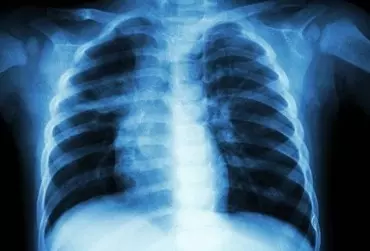

Aspiracja ciała obcego – pułapka w diagnostyce zapalenia płuc u dzieci

Opis przypadku niespełna dwuletniego chłopca, który był leczony w oddziale pediatrycznym z powodu zapalenia płuc. W czwartym dniu hospitalizacji przypadkiem się okazało, że dziecko zaaspirowało orzeszek. W dalszej części pracy opisano epidemiologię, objawy, diagnostykę i postępowanie w przypadku aspiracji ciała obcego, zwrócono uwagę na jej powikłania, poruszono problem błędnej lub opóźnionej diagnozy.